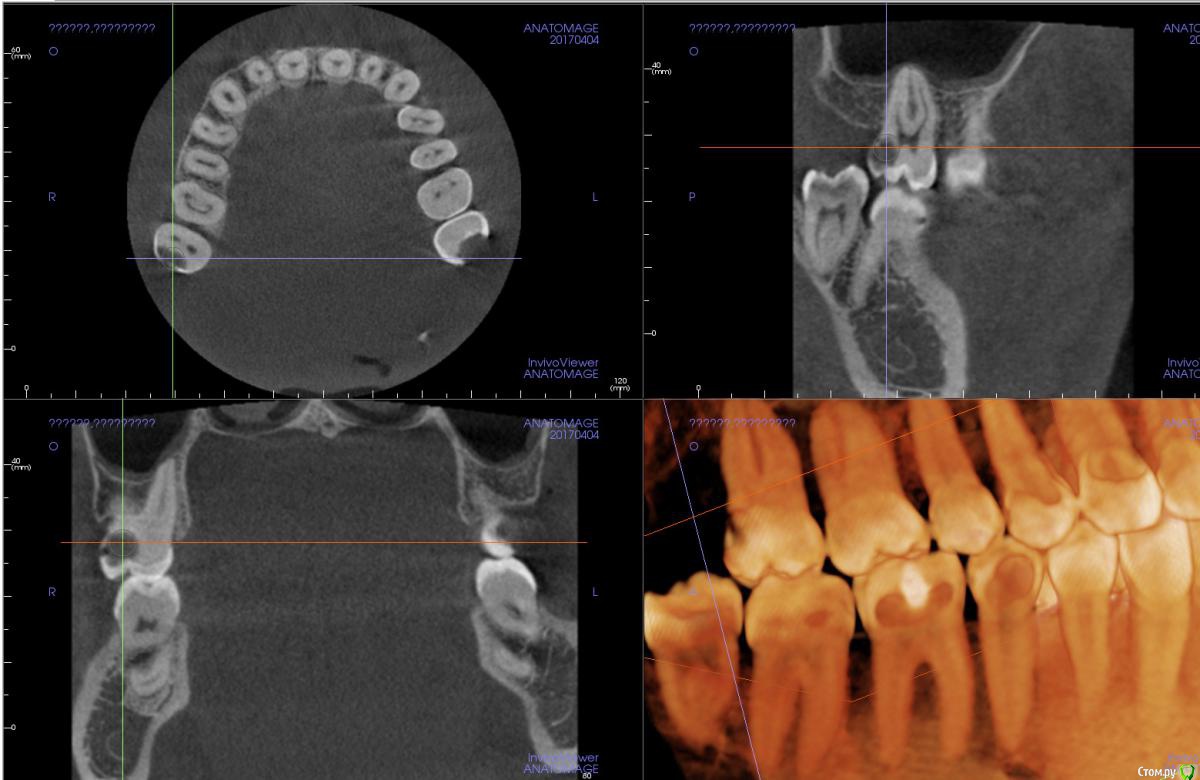

Xealer Опубликовано 20 апреля, 2017 Поделиться Опубликовано 20 апреля, 2017 (изменено) Здравствуйте! Меня зовут Руслан, мне 31 год.Меня 2 месяца назад стал беспокоить зуб 27.Моя цель: вылечить зуб 27 с минимальным вмешательством, сохранить нервы в пульпе. После этого вылечить зуб 17.Предыстория в спойлере:удалено администраторомТеперь зуб частично разрушен, видимо пломба отвалилась. Диагноз - пульпит.До этого боль была ноющая, сильно не беспокоила.Вчера полчаса болел сильно, сейчас снова утихла.Вопрос 1: Означает ли это, что пломба была установлена плохо?Стал ходить по разным стоматологам, с хорошей репутацией(подробности в спойлере) удалено администраторомудалено администраторомбыл только на консультациях: удалено администратором Сказал, что нужно сделать 3d томографию всех зубов и ставить коронку на 27. Цена 10 тыс руб. удалено администратором(стаж более 25 лет, высокая репутация в интернете): Посмотрел 3d томографию, сказал, что лучше поставить коронку, но можно поставить пломбу! Когда, я спросил про материалы для коронки, сказал, что можно поставить: - металлокерамическую коронку (CoCr) - титан Стал немного путаться в цене. Отправил к стоматологу-терапевту удалено администратором, на первоначальное лечение перед установкой коронки. Цена 12 - 15 тыс руб. Про зуб 17 сказал, что коронку ставить не надо, можно поставить пломбу.удалено администратором удалено администраторомРассказал про лечение подробнее, чем остальные, показал фотографию разрушенного зуба. Сделал 3d томографию. Назвал высокие цены, сославшись на то, что в других стоматогиях некачественные материалы, а у них качественные немецкие материалы. Цена 34-50 тыс руб включает: Сумма в руб Изготовление культевой вкладки разборной либо за 8000, либо за 15000 Изготовление металлокерамической коронки (CoCr) - Некая стандартная цена 14000 (видимо стандарная цена в моём случае не использовалась, была на бланке) - Литьевой метод 20000 - Фрезерный метод 30000 и т д Про зуб 17 сказал, что коронку ставить надо, и ставить пломбу на него неграмотно с медицинской точки зрения, так как стенка до пульпы всего 1 мм. Остальные вопросы:2. Могут ли такие цены, которые мне предложили в удалено администратором за "качественные немецкие материалы", быть честными?3. Можно ли поставить пломбу на 27, сохранив пульпу?4. Если ставить коронку на 27, то какой материал выбрать? нужен ли титан?5. Достаточно ли на 17, поставить пломбу?6. Какого стоматолога порекомендуете? Во вложении я сделал скриншот срезов 27 и 17, где расстояние до пульпы минимально. Если надо могу выложить весь файл с 3d томографией. Изменено 25 апреля, 2017 пользователем red_butler Ссылка на комментарий

Pan Опубликовано 22 апреля, 2017 Поделиться Опубликовано 22 апреля, 2017 Ваш зуб требует эндодонтического лечения, требует ли Ваш зуб ортопедического лечения( коронки) трудно оценить по представленным снимкам. Даже если учитывать утрату тканей для эндо доступа, следует оценить оставшиеся ткани для возможной реставрации зуба без применения ортопедической конструкции. 1 Ссылка на комментарий

Xealer Опубликовано 8 ноября, 2020 Автор Поделиться Опубликовано 8 ноября, 2020 Посмотрите пожалуйста изображения с новой компьютерной томографией зуба 27.Не появился ли периодондит?https://gitlab.com/sputn/health_dataЗуб(если его ещё можно так назвать) не беспокоит. Ссылка на комментарий